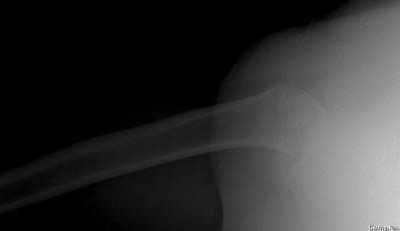

Пока я пользуюсь методикой принятой у нас (методика Сиэтла), также перкутанный спицевой метод, только сцицы 2.8 мм с резбой на конце.

Здесь случай перелома-вывиха плеча, больному 56 лет, после "дважды" закрытой неудачной репозиции, опять же ургентно взяли в операционную, после полного общего обезболивания попытались сделать репозицию, и фиксацию провели спицами.

Больной находился в повязке, примерно напоминяющей косыночную, рекомендованы движения в локтевом суставе и маятниковые движения в плече, спицы удалены в три недели (были случаи миграции)

Больной амбулаторный, предупрежден на случай осложнения АВН головки.